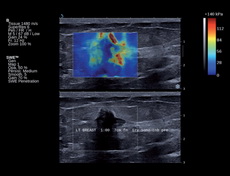

UltraFast Doppler vascular